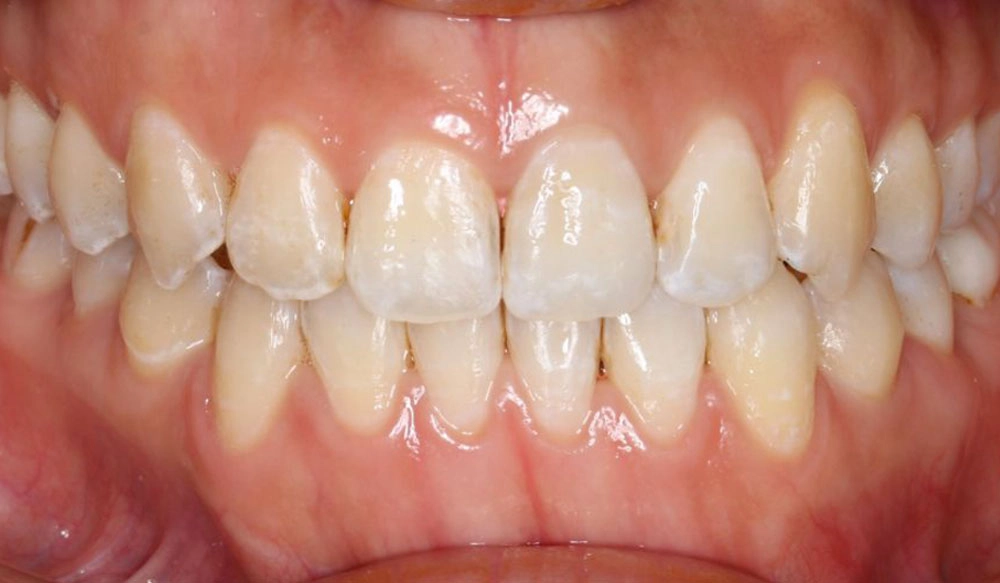

Crowding

Crowding is the condition in which there is a discrepancy between tooth size and space available for the teeth to be aligned in the dental arch

Patient Information:

Age: 17

Gender: female

Invisalign Treatment Option: Invisalign Comprehensive

Total Treatment Time:

29 months